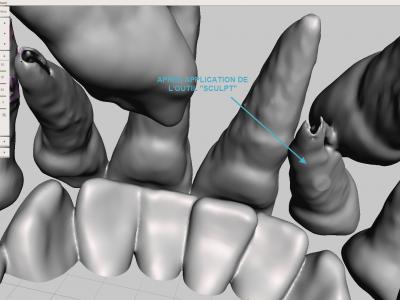

- Etape de finitions : reboucher des manques, adoucir des pics ou des crêtes avec les différents outils "Sculpt"